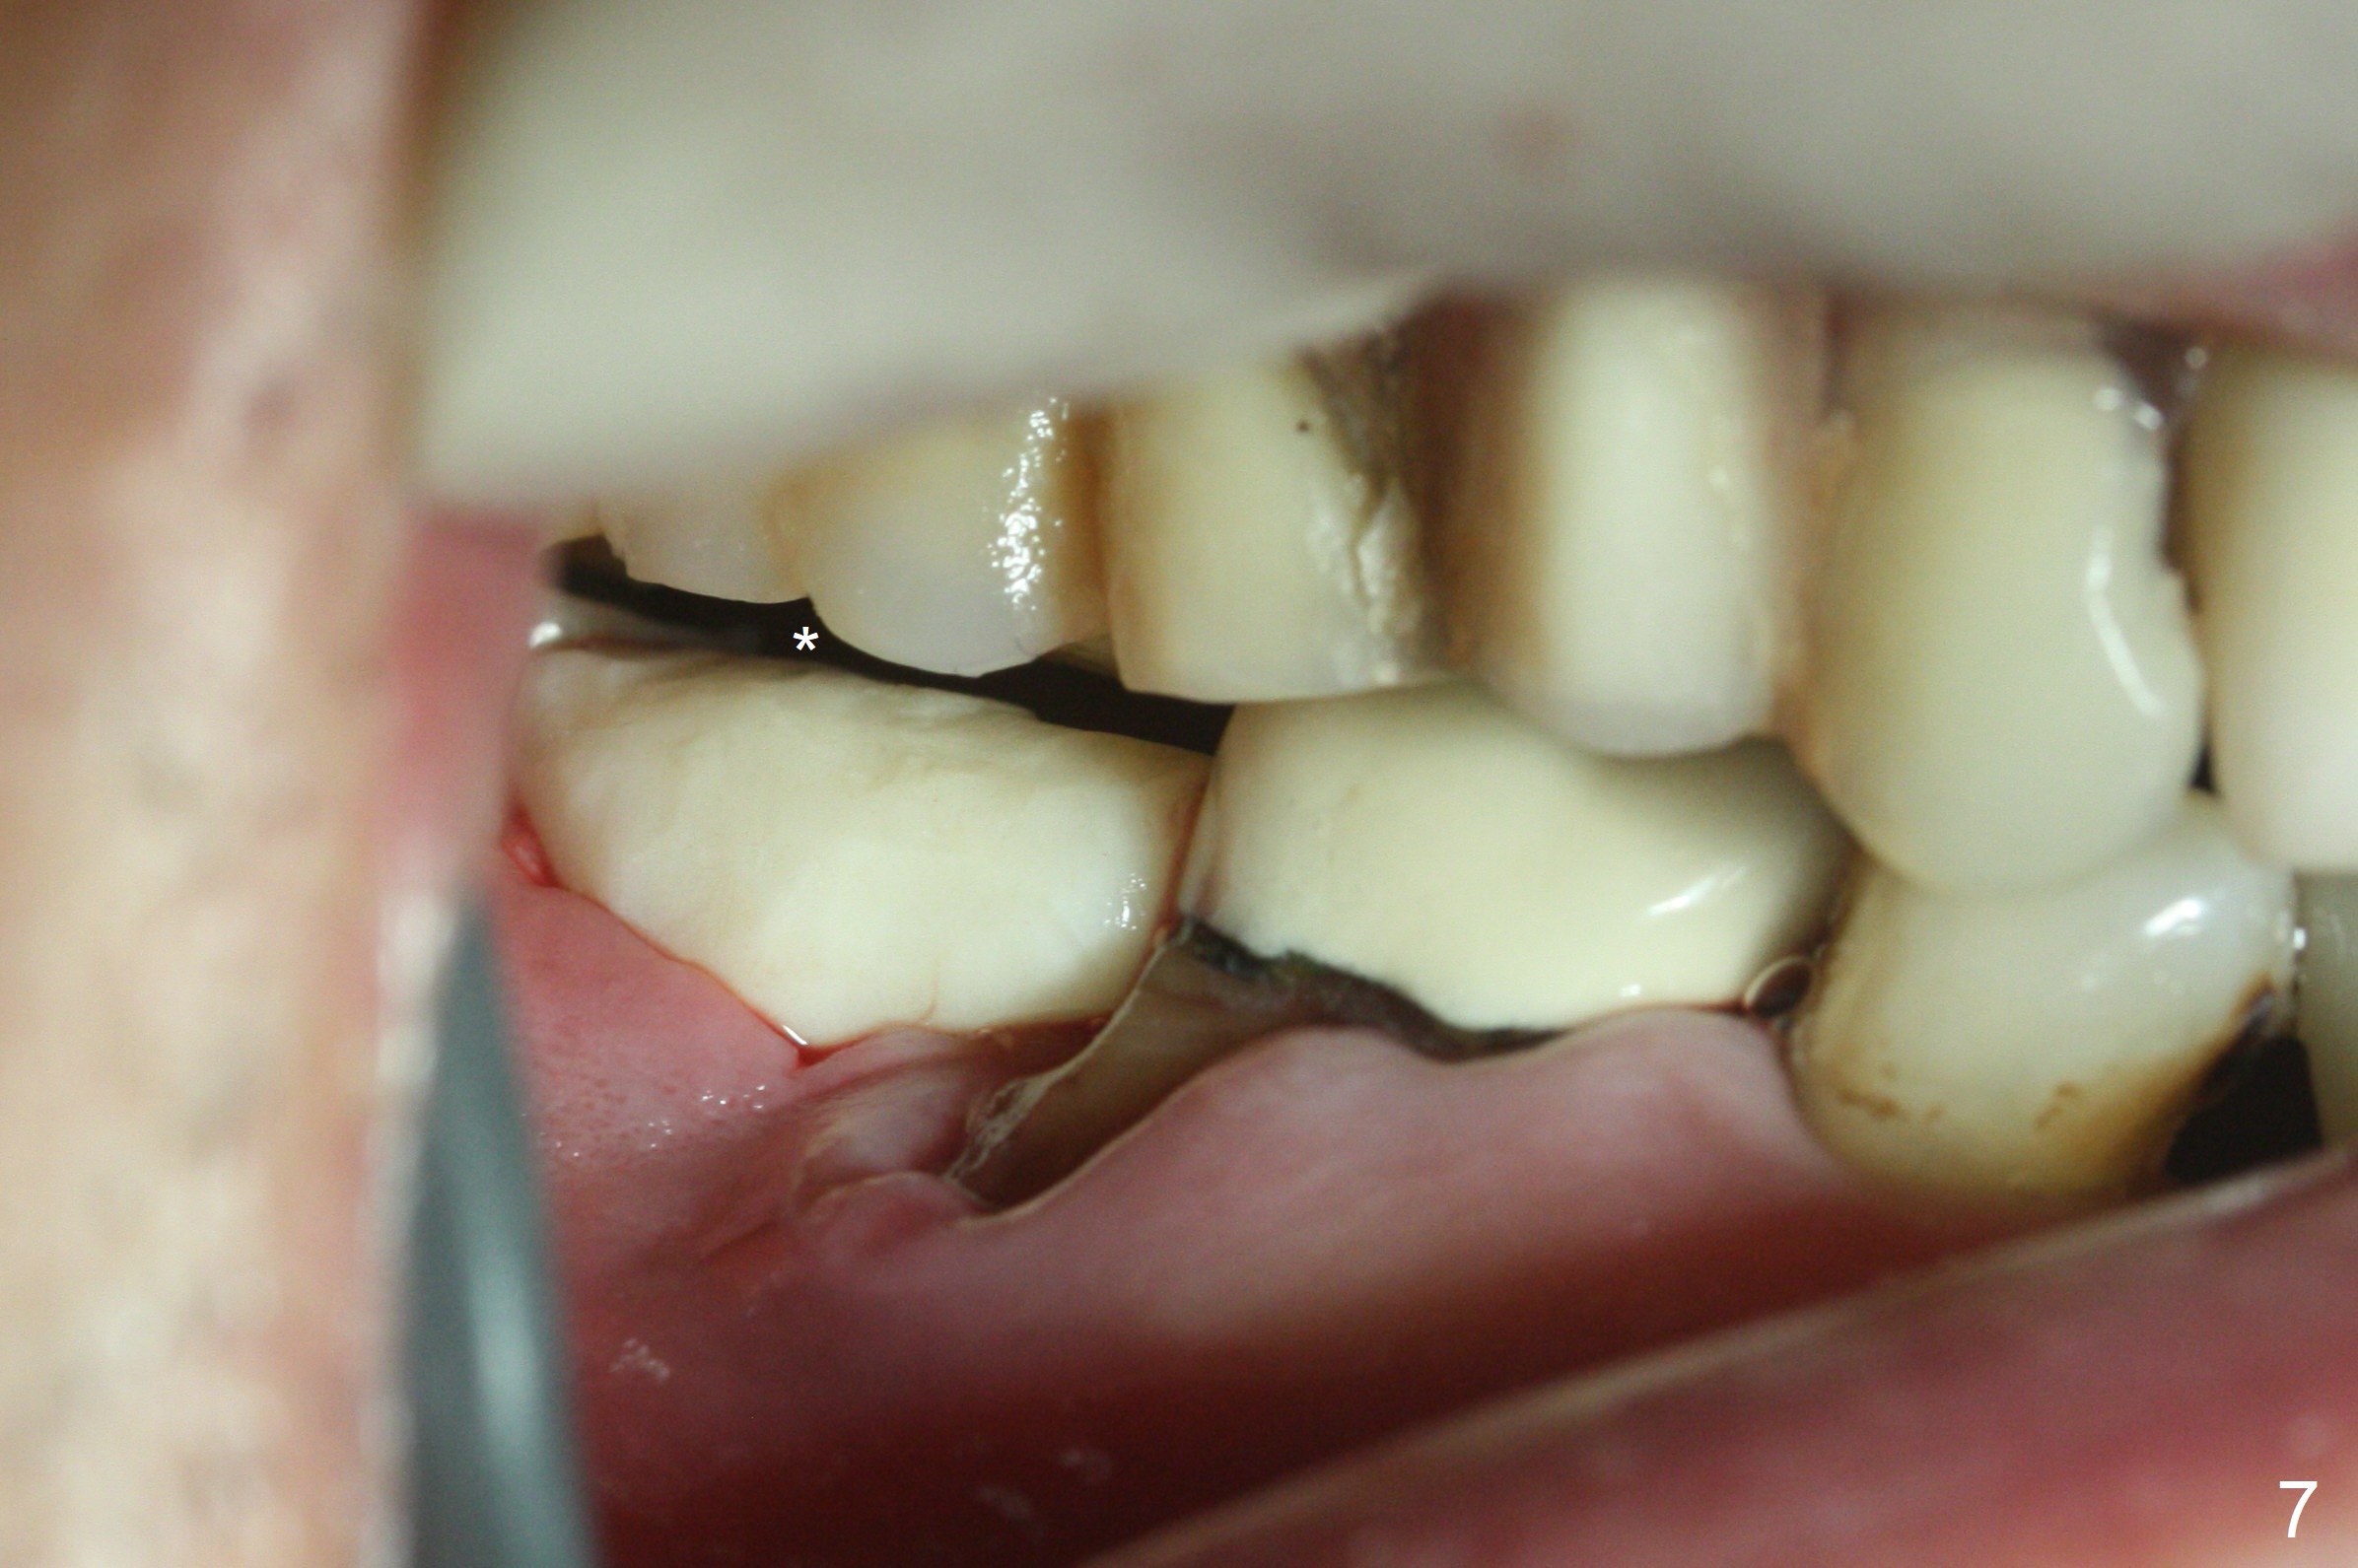

Although the tooth #30 has distobuccal root exposure (Fig.1 <), it is asymptomatic. In contrast the tooth #31 with the distoocclusal caries (*) is symptomatic. After use of 2 mm drill for 18 mm (lingual gingival margin), a calculated parallel pin is inserted (Fig.2 (D: 2 distal roots of the tooth #30)). It appears that a 11.5 mm long implant is appropriate for the site; a 5 mm cuff is expected. Following 4.8 mm drill, a 5.5x11.5 mm implant is placed initially (Fig.3) with an apical space (*) and clearance from the Inferior Alveolar Canal (red dashed line). The implant is placed deeper with placement of a 6.5x4(5) mm abutment and bone graft (*, Fig.4,5). After placement of collagen membrane over the graft, an immediate provisional is fabricated (Fig.6 P) with clearance from the opposing tooth (Fig.7 *). There is no bone loss 3.5 months postop (Fig.8). In fact the abutment has not been seated completely since its placement (Fig.4,5,8). The crown/abutment dislodges 3 years 3 months post cementation (Fig.9). The latter occurs for long incubation time because of opposing partial denture (Fig.10). After trimming proximal surfaces (Fig.11: arrowheads), the abutment remains incompletely seated (Fig.11) due to possible crestal bone interference (Fig.11 *). The smaller abutment by itself remains unseated (Fgi.12). One size small one is completely seated (Fig.13). Impression is taken. Two weeks later the abutment margin is supragingival. After screw torque at 20 Ncm, the crown is cemented with access hole. Excess cement is removed.